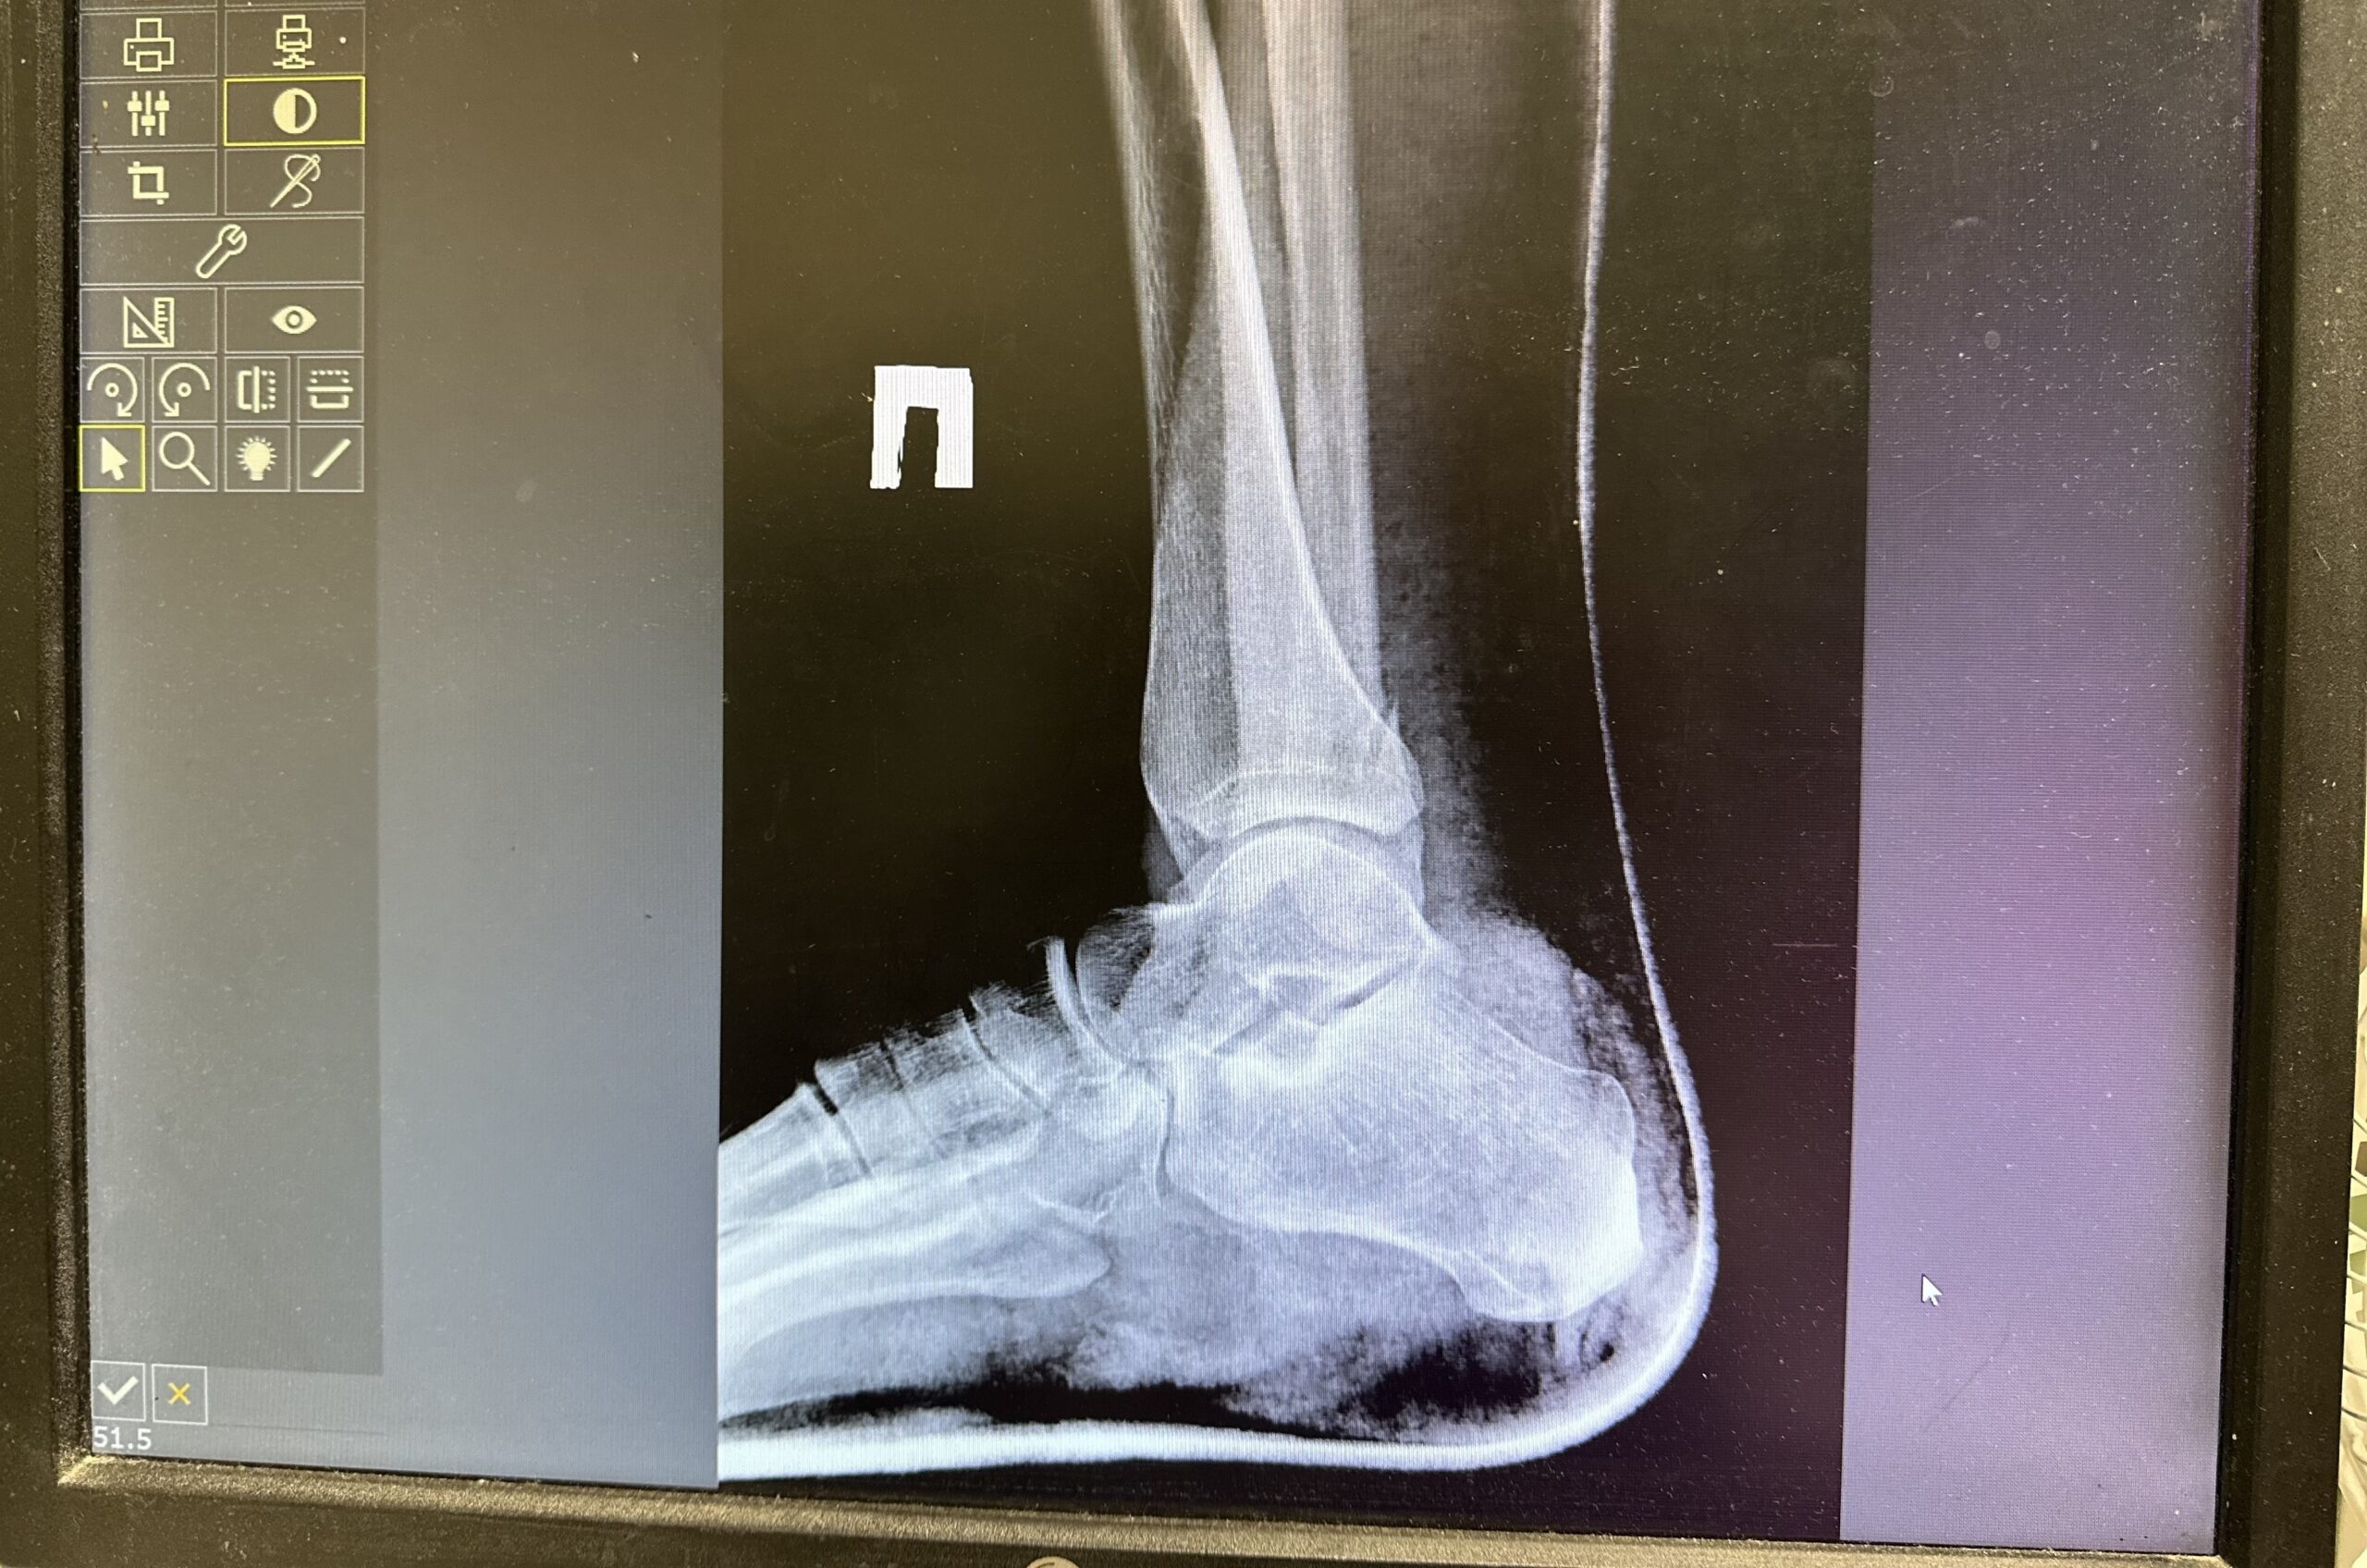

Инцидент произошел во время имущественного спора. Женщина в сопровождении подруг приехала к бывшему мужу, чтобы забрать вещи, которые пропали с ее дачи после развода. В ходе ссоры она избила новую сожительницу бывшего супруга, вышедшую на шум. В результате потерпевшая получила множественные переломы обеих ног.